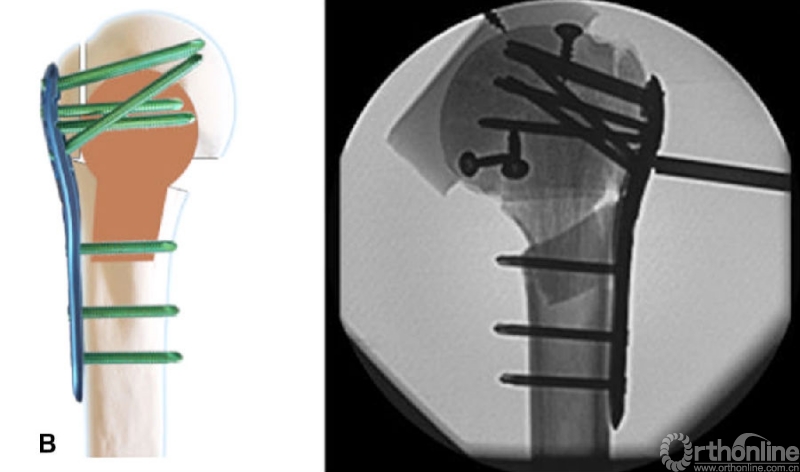

笔者团队在2010年首次提出肱骨近端解剖髓内支撑概念[8,12],并以此概念使用修整后的解剖型异体腓骨(图1)进行临床试验,腓骨支撑组随访33.5(24-48)个月,解剖腓骨支撑无头内翻与螺钉切割,总体肱骨头坏死率为10.6%,但因患者满足当前功能,均未行翻修手术,术后2年功能优良率达100%。通过形态学研究[13]分析并比较了老年和年轻患者的髓腔解剖退变模式,以更好地从解剖学上了解肱骨近端髓腔形态,完善解剖髓内支撑概念。通过有限元分析[14]对比解剖髓内支撑结构联合锁定钢板能够较锁定钢板获得更好的抗剪切与抗扭转力。为了摆脱同种异体骨资源限制,团队设计研发了髓内支撑钉与钢板系统(图2)[9],并应用于老年Neer3/4部分肱骨近端骨折,结果显示手术时间与术中出血量与单纯钢板治疗无差异,1年以上随访显示畸形愈合率11.1%远低于钢板组,Constant评分、DASH评分、患者主观优良率均高于钢板组。

图1 解剖型异体腓骨

图2 髓内支撑钉与钢板系统